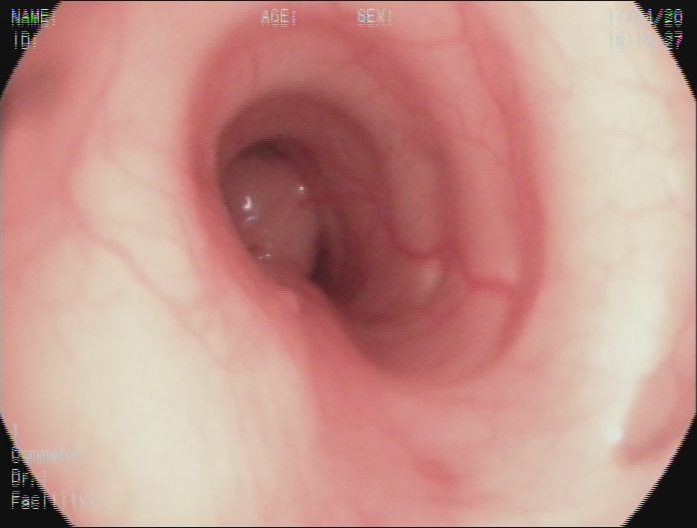

左主支气管结节,表面光滑

两年前38岁的王女士健康体检,发现左主支气管7×10mm结节,遂到我院就诊,支气管镜检查见左主支气管内带蒂结节,表面光滑。经支气管镜使用圈套器完整切除结节,结节根部冷冻冻融治疗。病理提示为低度恶性的类癌。近日复诊,胸部CT、支气管镜检查均未见肿瘤复发。